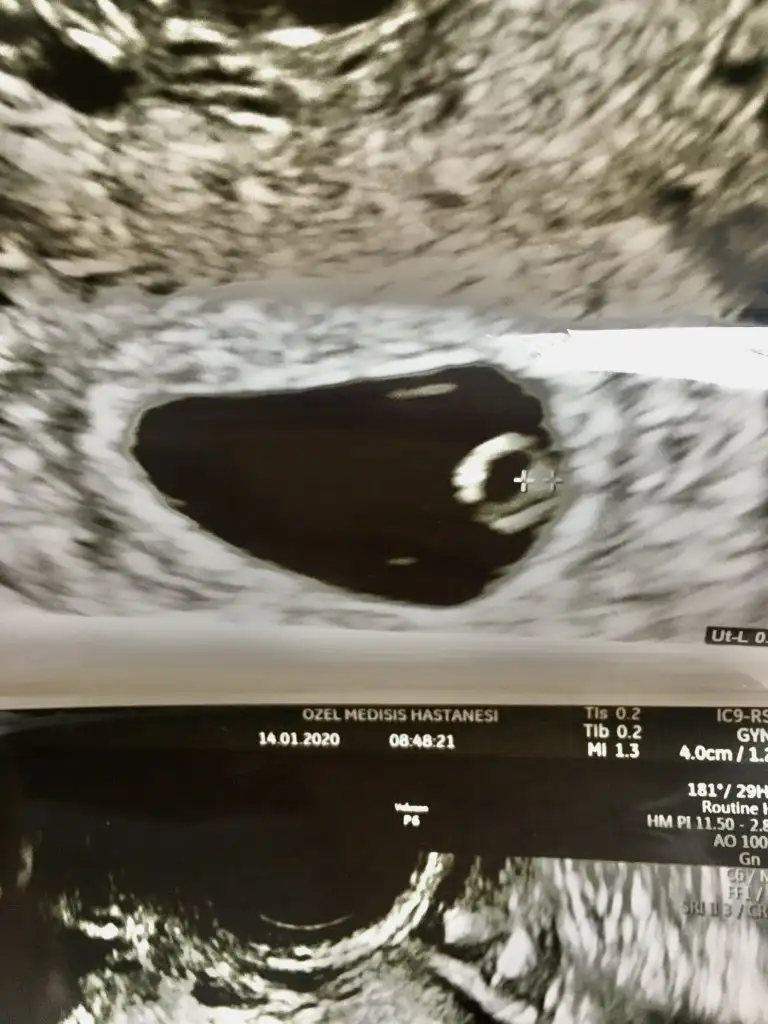

Merhaba kızlar. Şimdi kontrolden eve döndüm. 5+5im vajinal muayene oldum yolk oluşmuş ve bebeğimde gelişime başlamış. Siz ultrason fotoğrafımı da göstereyim. Yalnız bir sorun var, tiroidim yüksek çıktı ve doktorum beni hemen dahiliyeye yönlendirdi. Doktor tiroid ultrasonu istedi ve ultrasonda nodülüm olduğu saptandı. Düzensiz olduğu için kötü huylu olabileceği söylendi. İlaç tedavisine başlandı. Bu ayrı bir üzüntüm tiroidimin yüksek çıkması ayrı bir üzüntüm. Kontrol altına alınmazda bebekte bir çok sıkıntıya sebebiyet verebiliyormuş. Çok çok canım sıkkın.

Eklentiler

• B6AF0DC5-7282-4647-B33F-9A6AE2759B2E.webp

40,5 KB · Görüntüleme: 75